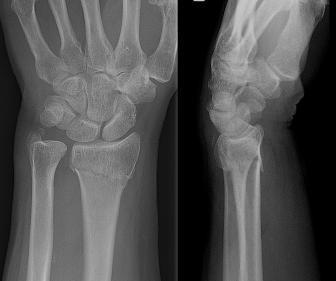

What is this?

Colle’s Fracture

Fracture of distal radius with dorsal displacement of fragments